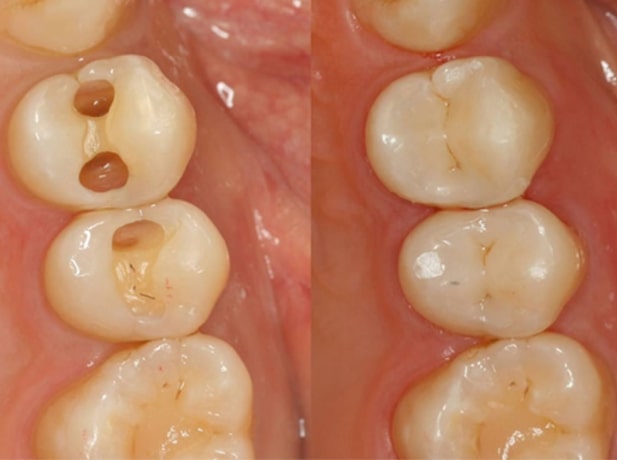

Sâu răng hiểu đơn giản là tình trạng xuất hiện những lỗ hổng ở răng, gây nhét thức ăn và khó chịu, đau nhức khi ăn nhai. Trước khi trám răng, bác sĩ sẽ làm sạch toàn bộ mô răng bị sâu và thay thế bằng vật liệu có tính chất sinh học gần giống với mô răng nhất.